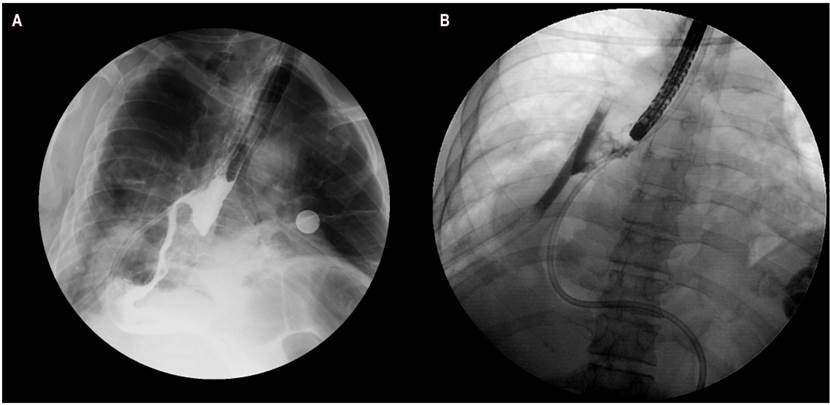

Hombre de 69 años con antecedente de adenocarcinoma gástrico, con extensión a la unión gastroesofágica, estadificado III b (pT4N0M0), con antecedente de diabetes mellitus. El paciente se llevó a esofagogastrectomía por laparoscopia y toracoscopia con bordes de sección negativos, en manejo con adyuvancia y protocolo Capeox. Presentó disfagia orofaríngea y odinofagia, así como pérdida de peso de 18 kg. En el día 11 posoperatorio presenta signos de respuesta inflamatoria, con esofagograma, que evidenció una fístula a nivel de anastomosis. El estudio endoscópico mostró hallazgo de fístula de 15 mm en la anastomosis a los 30 cm de las arcadas dentarias; bajo visión fluoroscópica presentó extraluminización fuera de la pared esofágica (Figura 1). El manejo inicial consistió en la colocación de 5 clips. Debido a la friabilidad de la mucosa no se logró el cierre total del defecto.

Figura 1 A. Esofagograma: trayecto fistuloso en la anastomosis esofagogástrica. B. Irrigación del medio de contraste, con extraluminización fuera de la pared esofágica.